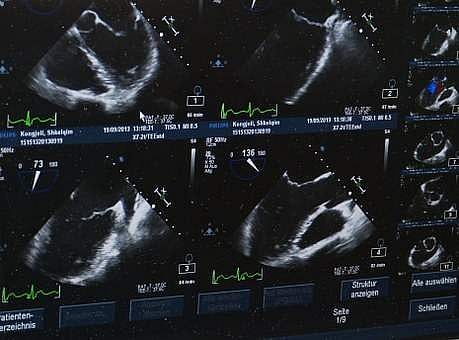

Image used for representational purpose

NEW YORK: Earlier detection is important to improving survival of patients with liver cancer, and combining an ultrasound imaging with a blood test can help achieve that, say researchers, including one of Indian-origin.

Using ultrasound and a blood test for high alpha fetoprotein (AFP) levels together improves detection of early-stage liver cancer significantly, said the study published in the journal Gastroenterology.

"Liver cancer screening in patients with chronic liver disease has traditionally been performed using an abdominal ultrasound. While ultrasound is readily available and noninvasive, it misses many cancers when they are small," said Amit Singal, associate professor at the University of Texas Southwestern Medical Centre.

"Our study found that adding the blood biomarker alpha fetoprotein increased detection of early-stage hepatocellular carcinoma from 45 per cent with ultrasound alone to 63 per cent using the two tests in combination," Singal said.